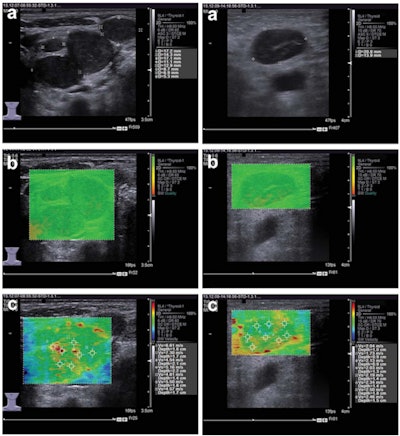

The researchers sought to assess the performance of Virtual Touch tissue imaging quantification (VTIQ) software (Siemens Healthineers) for the differential diagnosis of cervical lymph nodes. They retrospectively analyzed the conventional ultrasound and VTIQ images of 85 patients at Changhai Hospital from November to December 2015 who had superficial lymph-node lesions and a pathologically confirmed diagnosis.

The patients first received conventional 2D ultrasound exams using an Acuson S3000 ultrasound scanner (Siemens) and a 4- to 9-MHz transducer. Next, the lymph nodes' shear-wave velocity values were measured using the VTIQ software, which is based on acoustic radiation force impulse (ARFI) elastography. All studies were performed by a physician with extensive qualifications and experience in sonographic diagnosis, according to the researchers. Final pathologic diagnosis was later conducted on all nodes after either surgery or aspiration biopsy.

The metastatic lymph nodes had a mean shear-wave velocity of 4.29 ± 1.23 m/sec, while nonmetastatic nodes had a mean shear-wave velocity of 2.58 ± 0.50 m/sec. The difference was statistically significant (p < 0.001). The researchers generated a receiver operating characteristic (ROC) curve to determine the software's efficacy for the differential diagnosis of these lymph nodes.

Metastatic and nonmetastatic lymph nodes present differently on shear-wave elastography, the authors concluded.